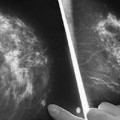

Բժիշկ-օնկոլոգի խորհուրդը. 6 մթերքներ, որ կրծքի քաղցկեղի հզոր թշնամիներն են